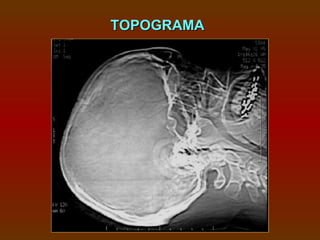

TOPOGRAMA

ESTUDO DO POLÍGONODE WILLIS  1 mm espessa X 1 mm incremento.  Em média 100 ml de contraste, a 3ml/s.

• 41.

A marcação vaida base do seio esfenoidal ao topo do corpo caloso.